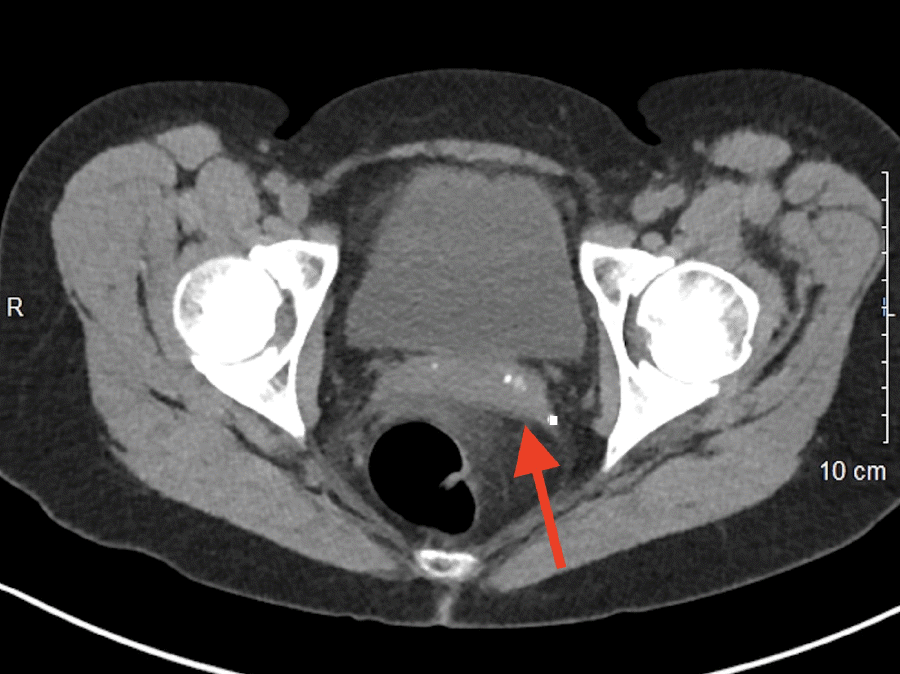

Initial hemoglobin and hematocrit were 9.2 g/dL and 27.5%, respectively, and the WBC was 22,200/mm3. Creatinine was 3.6 mg/dL, and BUN was measured at 44 mg/dL. No prior laboratory values were available for comparison. A non-contrast CT scan of the abdomen and pelvis was obtained due to elevated creatinine, which showed a grade IV splenic rupture according to the American Association for the Surgery of Trauma (AAST) splenic injury scale. The parenchymal hematoma was reported to be 12 × 15 cm with a large halo of blood around the liver (Figure 1). A moderate amount of blood was also evident in the pelvis (Figure 2). Operative management was pursued versus nonoperative means due to the grade of the splenic rupture and the amount of blood in the abdomen.

Figure 2. CT of Pelvis Demonstrating Free Blood Around Rectum (arrow). Published with Permission

CT of Pelvis Demonstrating Free Blood Around Rectum (arrow).